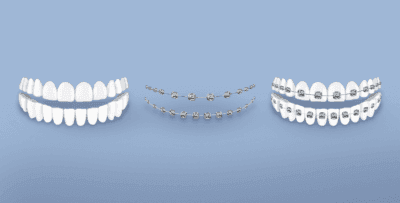

أنواع تقويم الأسنان المعدني

هناك العديد من أنواع تقويم الأسنان المعدني التي يمكن الاعتماد عليها، وهي:

- تقويم الأسنان المعدني التقليدي:

يعتبر الأكثر شيوعًا والأقل تكلفة، كما أنه أسرع وأكثر فعالية، ويتم فيه استخدام خرزات معدنية تثبّت على الأسنان عبر مادة لاصقة، ومن ثمّ يتم ربط الخرزات المتجاورة باستخدام سلك معدن، كما أنه يتم استخدام عقدة تثبيت لتأمين تموضع السلك.

- تقويم الأسنان المعدني البسيط:

يعتبر هذا التقويم ذاتي الإغلاق مقارنةً بتقويم الأسنان المعدني التقليدي، كما أنه يتألف من قوس معدني يتم تثبيته بالأسنان عبر خرزات ليست بحاجة لربط من أجل تثبيت السلك عليها، ولكن لها قفل يثبّت من خلال إغلاق السلك المعدني بموضعه فوق الخرزات.

مكونات تقويم الأسنان المعدني

يتكون تقويم الأسنان المعدني مما يلي:

- قطع معدنية صغيرة تعرف بالحمالات وتُلصق بالسن بشكل مباشر.

- سلك معدني يُدخَل بمنتصف القطع المعدنية التي تلتصق بالسن من أجل ربط الحمالات الملتصقة مع بعضها بأسنان الفك، كما يُشَد هذا السلك من فترة لأخرى.

تقويم الأسنان المعدني بالصور